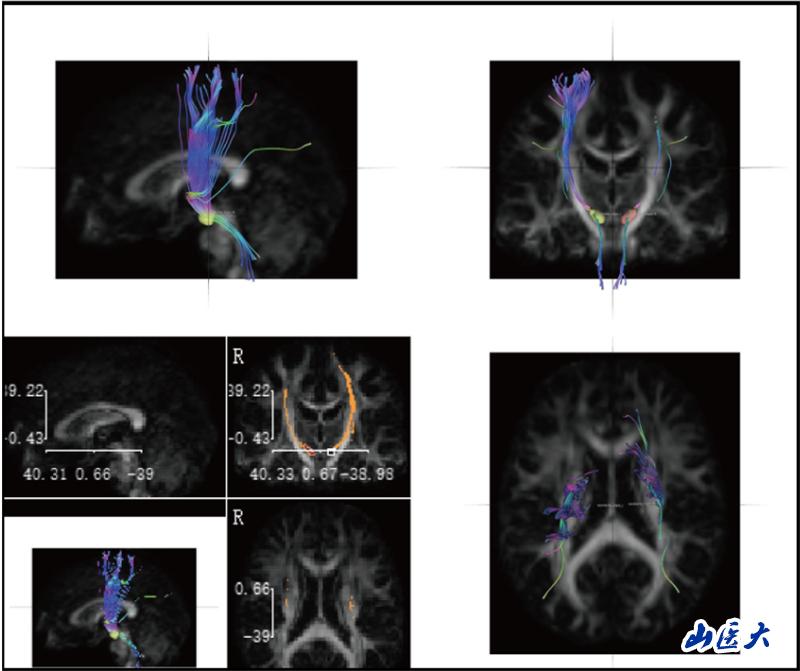

近日,我校基础医学院联合第二临床医学院,协同香港大学、南京医科大学和长治潞安医院,在医学教育国际期刊《Advances in Medical Education and Practice》发表题为“Enhancing Neuroanatomy Teaching with DSI Studio's Fiber Reconstruction Technology”的论文。我校基础医学院解剖教研室曾俊峰讲师为第一作者,陆利教授与成晓龙教授为共同通讯作者。

神经解剖学教学长期面临"结构隐匿性"与"空间复杂性"的双重挑战。传统的大体标本和平面模型难以展现纤维束、核团等微观结构的空间关系,易导致学生神经解剖结构认知困难。研究团队针对这一痛点,创造性引入前沿神经影像技术—DSI Studio纤维束成像系统。该技术通过对扩散磁共振成像(dMRI)数据分析,实现纤维路径智能追踪、三维动态重建及多维度交互可视化,构建起"影像解剖-病理对照-临床关联"的一体化数字教学体系。

研究团队创新性构建"理论-操作-临床"三阶整合教学模式,基于DSI Studio纤维束成像技术开展教学实践。选取38名低年级医学生为对象,通过整合人类连接组计划(HCP)标准脑数据库、帕金森病进展标志物计划(PPMI)及临床脑出血病例影像数据,建立"正常-病理"双模态教学资源库。此教学实践改革,不仅提升了学生神经解剖结构的空间理解力,并培养了学生从解剖结构认知到功能损伤解析的临床思维能力。

陆利教授团队长期致力于神经退行性疾病研究,此次将神经前沿进展转化为教学资源,实现了"科研数据教学化、教学过程科研化"的良性循环,使学生掌握解剖基础知识的同时,还可以智能化观察病理状态下的神经结构,为培养早期临床思维提供创新路径。